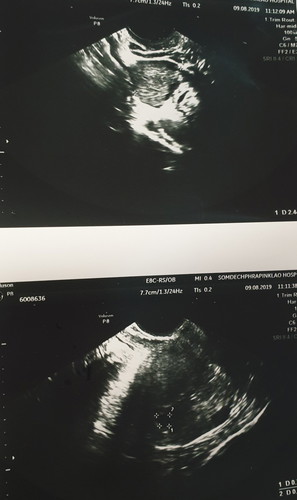

ตอนนี้ท้อง5week แล้วค่ะ ตรวจhcgได้ 5,500 ซาวด์ครั้งที่2 แล้วได้ผลตามภาพ คุณหมอยังไม่ให้ฝากครรภ์ นัดซาวด์อีกครั้งอีกสองสัปดาห์ กังวลมากๆเลยค่ะ "คุณหมอบอกพบถุง น่าจะเป็นถุงตั้งครรภ์? แต่ไม่ชัดเจน" ยิ่งกลัวเข้าไปใหญ่ มีใครเคยซาวด์แล้วได้ผลแบบนี้ไหมคะ ช่วยให้คำแนะนำด้วยค่ะ ขอบคุณมากๆค่ะ

5 วีค ยังเล็กมากจ้า เป็นไปได้สูงมากๆที่จะยังไม่เห็น ซาวด์ทางหน้าท้องหรือช่องคลอดคะแม่ ถ้าทางหน้าท้อง ถ้าตัวอ่อนยังเล็กมากๆ หรือเป็นคนหน้าท้องหนา อาจจะยังไม่เห็นค่ะแม่ ทางช่องคลอดจะพอมีลุ้นมากกว่าค่ะ ทั้งนี้เป็นไปได้ว่า อายุครรภ์อาจจะน้อยกว่าที่นับ เพราะไข่อาจจะตกช้ากว่ากำหนด ตัวอ่อนยังเล็กมากอยู่ จึงยังไม่พบ ก็เป็นได้ค่ะแม่ ทานโฟลิคทุกวัน พักผ่อนเยอะๆ นะคะ ซาวด์ครั้งหน้าอาจจะได้เจอกันแล้วจ้า